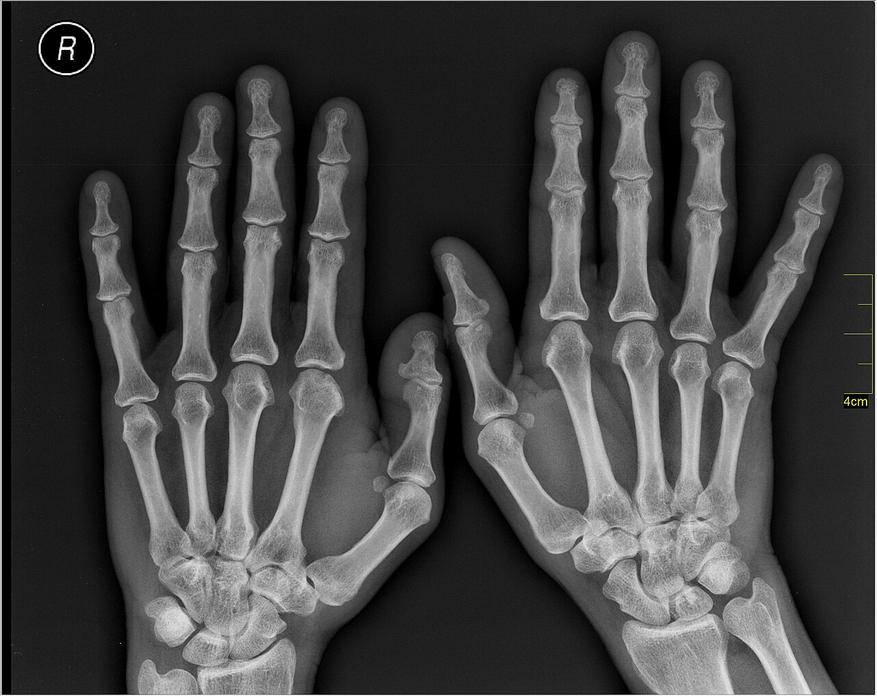

В основе такой «невидимости» алмаза лежат законы физики, а точнее взаимодействие (прохождение) рентгеновского излучения с различными химическими элементами. Чем больше атомный номер элемента, тем сильнее этот элемент поглощает рентгеновские лучи. Чем сильнее поглощение, там меньше засвечивается это место на негативе, тем оно светлее. Именно этот принцип и используют в рентгенодиагностике. Рентгеновские аппараты в поликлиниках настраиваются так, чтобы мягкие ткани человека, состоящие в основном из «легких» элементов (водорода с атомным номером «1», углерода, атомный номер которого «6», азота, с его «7» и кислорода с номером «8»), выглядели на черном фоне рентгеновских снимков сероватыми и почти прозрачными. А вот кости, в составе которых присутствует «тяжелый» кальций с атомным номером «20», наоборот, «задерживали» излучение и оставляли на снимке четкий светлый (белый) силуэт. Чем «тяжелее» элемент, чем больше его атомный номер, тем белее он будет выглядеть на снимке, ведь лучи почти не пробиваются через них к снимку и не «засвечивают» негатив.

Алмаз состоит из углерода, «легкого» элемента, который на рентгеновских снимках «прозрачен» и, соответственно, сливается с черным фоном снимка. Поэтому небольшой бриллиант на черном фоне снимка становится практически неразличимым. Его «прозрачность» на снимках — это всего лишь следствие низкого атомного номера углерода, а не какой-то мистической или «волшебной» особенности драгоценного камня.